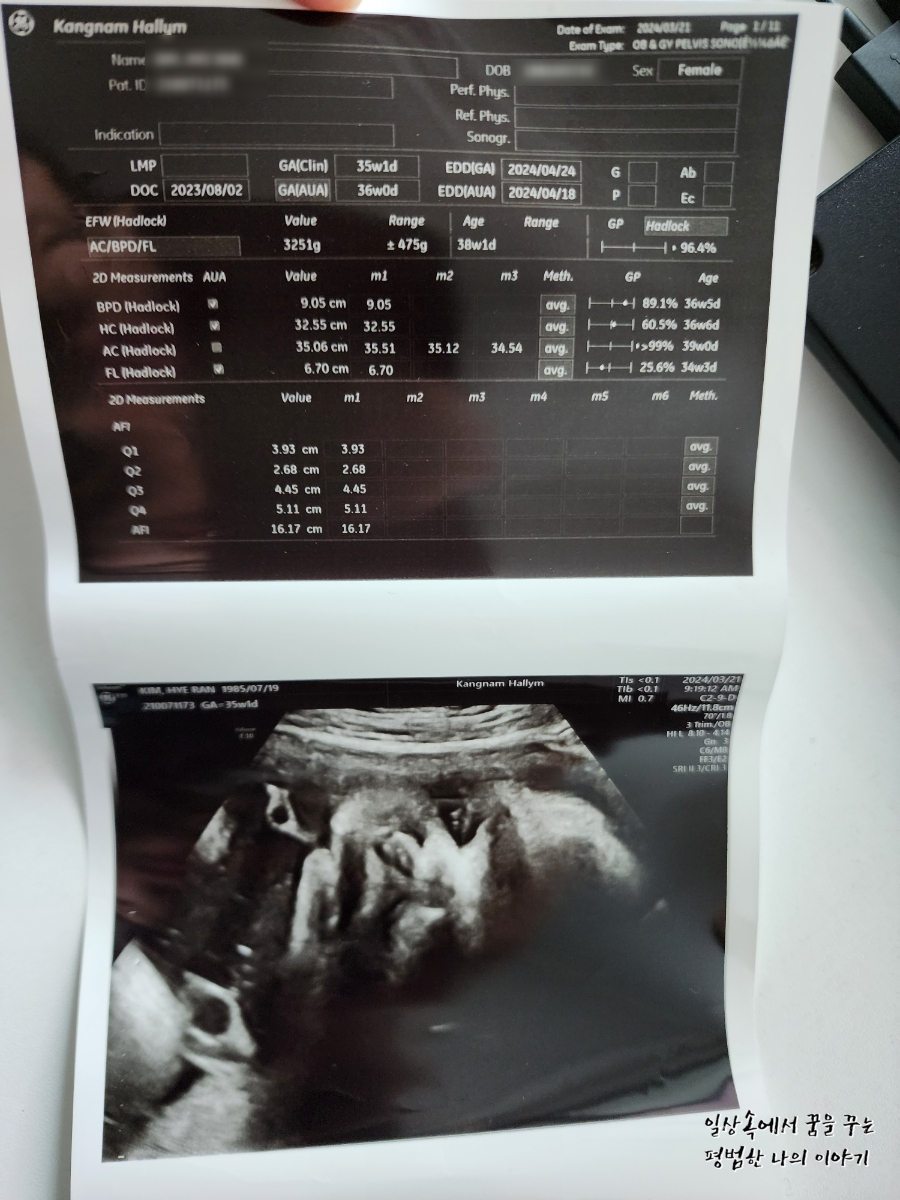

BPD(Biparietal Diameter, 위에서 볼 때 태아 머리 단면의 가장 긴 길이): 9.05cm

HC(Head Circumference, 태아 머리둘레): 32.55cm

AC(Abdominal Circumference, 배 둘레): 35.06cm

EDD(Expected Date of Delivery, 출산 예정일): 2024년 4월 24일

FL(Femur Length, 허벅지뼈 길이): 6.7cm

GA(Gestational Age, 임신 주차): 35주 차 1일

EFW(Estimated Fatal Weight, 태아 예상 체중)=EBW(Estimated Body Weight): 3251g

FHR(Fetal Heart Rate, 심장박동 수): 155bpm

CL(Cervical Length, 자궁경부 길이): 정상

AF(Amniotic Fluid, 양수): 정상